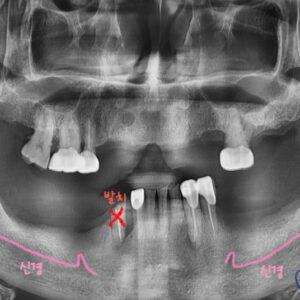

정확한 진단을 위해 파노라마 X-ray를 찍어 보았는데요.

빨간색 화살표 있는 부분의 치아를 보시면

어금니 치아 뿌리가 수직으로 파절되어있는 것을 확인할 수가 있습니다.

이렇게 뿌리가 파절된 경우에는

아쉽게도 치아를 살려서 치료할수가 없기 때문에 발치를 하셔야 합니다..ㅠㅠ

CT를 찍어서 확인한 결과,

발치와 동시에 임플란트가 가능한 상황이며,

약간의 뼈이식이 필요하다는 진단이 나왔습니다.